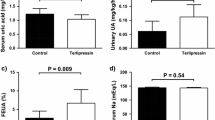

As described above, a minipump administering 30 ng AVP/h s.c. was implanted 2 days before the administration of an aquaretic treatment (tolvaptan or LIT01-196) or saline, and all animals received a semi-liquid diet (50% water, 50% gel diet, as described in “Methods”). Water consumption included water mixed with the food as well as water consumed from the bottle (experimental protocol; Fig. 5a). Four experimental groups were studied: the control group (receiving no AVP, n = 7), the AVP + saline group (continuous s.c. infusion of 30 ng AVP/h + saline 1 ml/kg s.c. on days 0 and 1, n = 13), the AVP + tolvaptan group (30 ng AVP/h s.c. + tolvaptan 900 nmol/kg s.c. on days 0 and 1, n = 12), and the AVP + LIT01-196 group (30 ng AVP/h s.c. + LIT01-196 900 nmol/kg s.c. on days 0 and 1, n = 9). On day 0, before treatment administration, plasma sodium levels were low and similar in all animals receiving AVP (103 ± 1, 103 ± 1, and 101 ± 3 mmol/l, p = 0.6, for the AVP + saline, AVP + tolvaptan, and AVP + LIT01-196 groups, respectively). Animals receiving AVP + saline had significantly lower urine output than controls (49% lower on average between days 1 and 2, P = 0.002), higher urine osmolality (355% higher, P < 0.001), lower water intake (59% lower, P < 0.001), and lower plasma sodium levels (27% lower, P < 0.001). These parameters remained stable from days 0 to 2 (Fig. 5b–e).

a Experimental protocol for generating hyponatremia. On day −2, a plasma sample was collected from the tail vein of each animal (male SD rats). Except for the control group, which received no AVP, a subcutaneous osmotic minipump delivering AVP at a rate of 30 ng/h was then implanted into each animal. All the animals were given semi-liquid food. On day 0, a plasma sample was collected and each animal treated with AVP received a s.c. injection of saline (green curve and triangles, 1 ml/kg, n = 13 animals), tolvaptan (red curve and diamonds, 900 nmol/kg, n = 12 animals), or LIT01-196 (blue curve and circles, 900 nmol/kg, n = 9 animals). Animals not treated with AVP received a s.c. injection of saline (black curve and squares, n = 7 animals). On day 1, plasma samples were obtained and each animal received another administration of the same treatment. On day 2, a final plasma sample was collected and the animals were killed. Urine output was measured and analyzed every day from days −1 to 2, and water and food intake were also measured daily. Change in 24-h urine output (b), urine osmolality (c), plasma sodium concentration (d), and water intake (including water in the bottle and in the food) (e) in animals receiving continuous s.c. AVP at a rate of 30 ng/h from days −2 to 2, and a s.c. injection of saline, tolvaptan, or LIT01-196 on days 0 and 1. Data are shown as mean ± SEM. Each group was compared with the AVP + saline group with a linear mixed-effects model, to take repeated measurements over time into account; *P < 0.05, **P < 0.01, and ***P < 0.001.

We then evaluated the effects of LIT01-196 in hyponatremic rats. The model was set up as described above, and LIT01-196 (900 nmol/kg s.c.) was administered on days 0 and 1. Relative to AVP-treated animals receiving saline, the LIT01-196-treated animals had significantly higher urine output (185% higher, on average, from days 1 to 2, relative to the AVP + saline group, P < 0.001), and lower urine osmolality (58% lower, P < 0.001). An increase in plasma sodium concentration was observed on day 1, 24 h after the first administration of LIT01-196, relative to animals receiving saline (109 ± 5 versus 100 ± 2 mmol/l), and on day 2 (110 ± 5 versus 100 ± 2 mmol/l), and plasma sodium concentration after LIT01-196 administration were significantly higher than in the AVP + saline group (P = 0.042). Following treatment with LIT01-196, AVP-treated animals had 177% higher levels of water consumption (including water in diet), on average, from days 1 to 2 (P < 0.001, versus the AVP + saline group) (Fig. 5b–e). LIT01-196 treatment was associated with a significant increase in food consumption, and thereby a significant increase in sodium intake. Body weight change from baseline was similar in AVP-treated animals receiving LIT01-196 and saline (Fig. S7). Subcutaneous administration of tolvaptan at the same dose (900 nmol/kg) on days 0 and 1 was associated with a similar effect on urine output, urine osmolality, plasma sodium, and water intake (Fig. 5b–e).